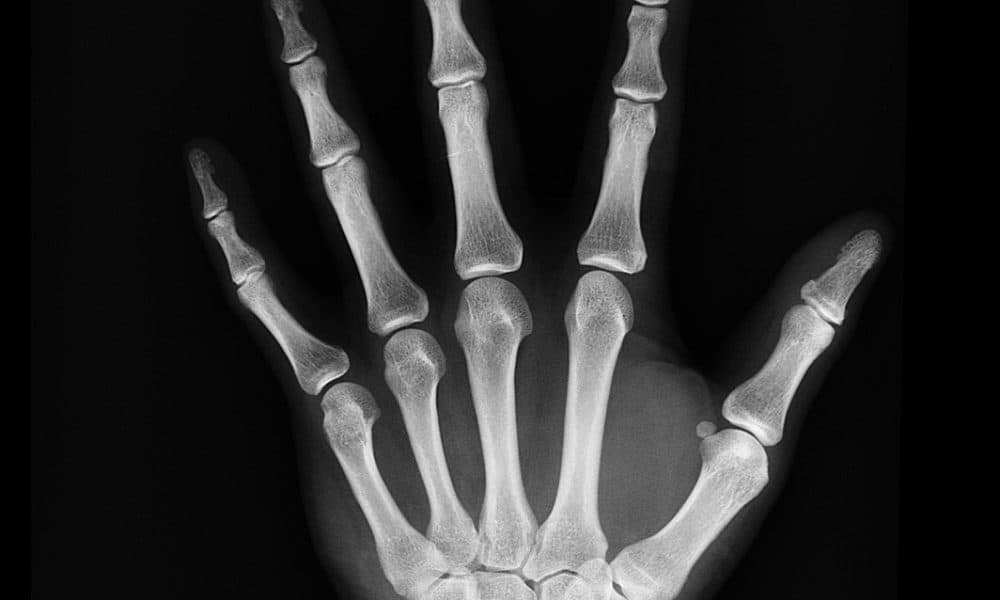

Radiobotics has extended its partnership with US teleradiology practice Virtual Radiologic (vRad), to develop a full suite of software algorithms to enhance the speed and accuracy of bone fracture X-ray studies.

Radiobotics develops AI models that can support timely and accurate diagnosis of fracture cases across the skeleton.

Bone fractures are a costly public health issue around the world, and a major burden to individuals, families, societies, and healthcare systems.